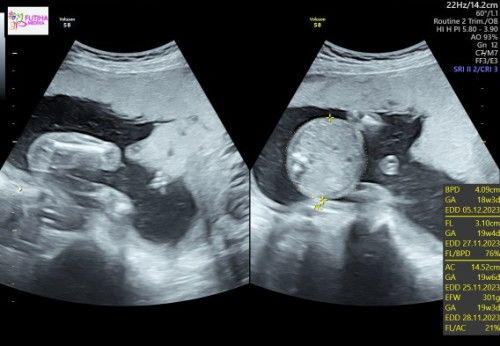

Hasil usg : BPD janin kurang 10 hari

Hallo mam, mau tanya, waktu usg usia kehamilan 20 minggu, tapi ukuran BPD (diameter kepala janin) kurang 10hari ( 18weeks 3day) ga sempet tanya dokter, karna pas usg belum sadar, dokter pun ngga menjelaskan karna fokus ke organ janin, tapi saya kepikiran terus mam, apakah ada yang sama ?